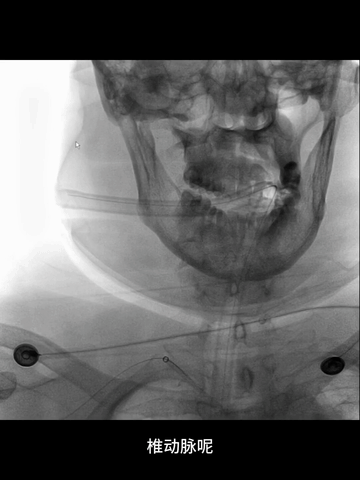

3、根据术前急诊CTA结果,左椎动脉颅内段显影不清,故决定经右椎动脉入路。

CTA:基底动脉闭塞,双侧胚胎型后交通,基底动脉尖部可见造影剂充盈;弓上血管迂曲明显,双侧椎动脉V1段均见明显曲折,左侧椎动脉颅内段显影不清,但可见右侧椎动脉颅内段延续至基底动脉闭塞近端。